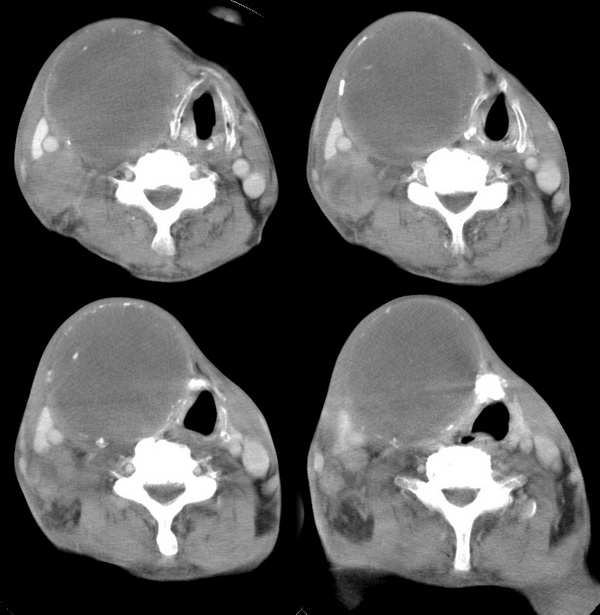

男,74岁,甲状腺肿30余年。现右颈部出现新肿块,疼痛,感乏力。

右颈部巨大软组织肿块影,范围较广,上至下颌角,下至颈静脉切迹。其最大层面位于右侧甲状腺区。肿块密度不均,其中有坏死液化区和班片状钙影,增强扫描见肿块实质区有强化。邻近结构挤压移位,部分结构侵蚀破坏,右侧多个颈深淋巴结肿大。两肺弥漫分布小结节影,以胸膜下为主,其大小不等,边缘光整。右侧胸壁亦见软组织结节影,纵隔多个淋巴结肿大及两侧锁骨上淋巴结肿大。

意见:右侧甲状腺癌并两肺、胸壁、纵隔淋巴结、颈深淋巴结、锁骨上淋巴结等广泛转移。